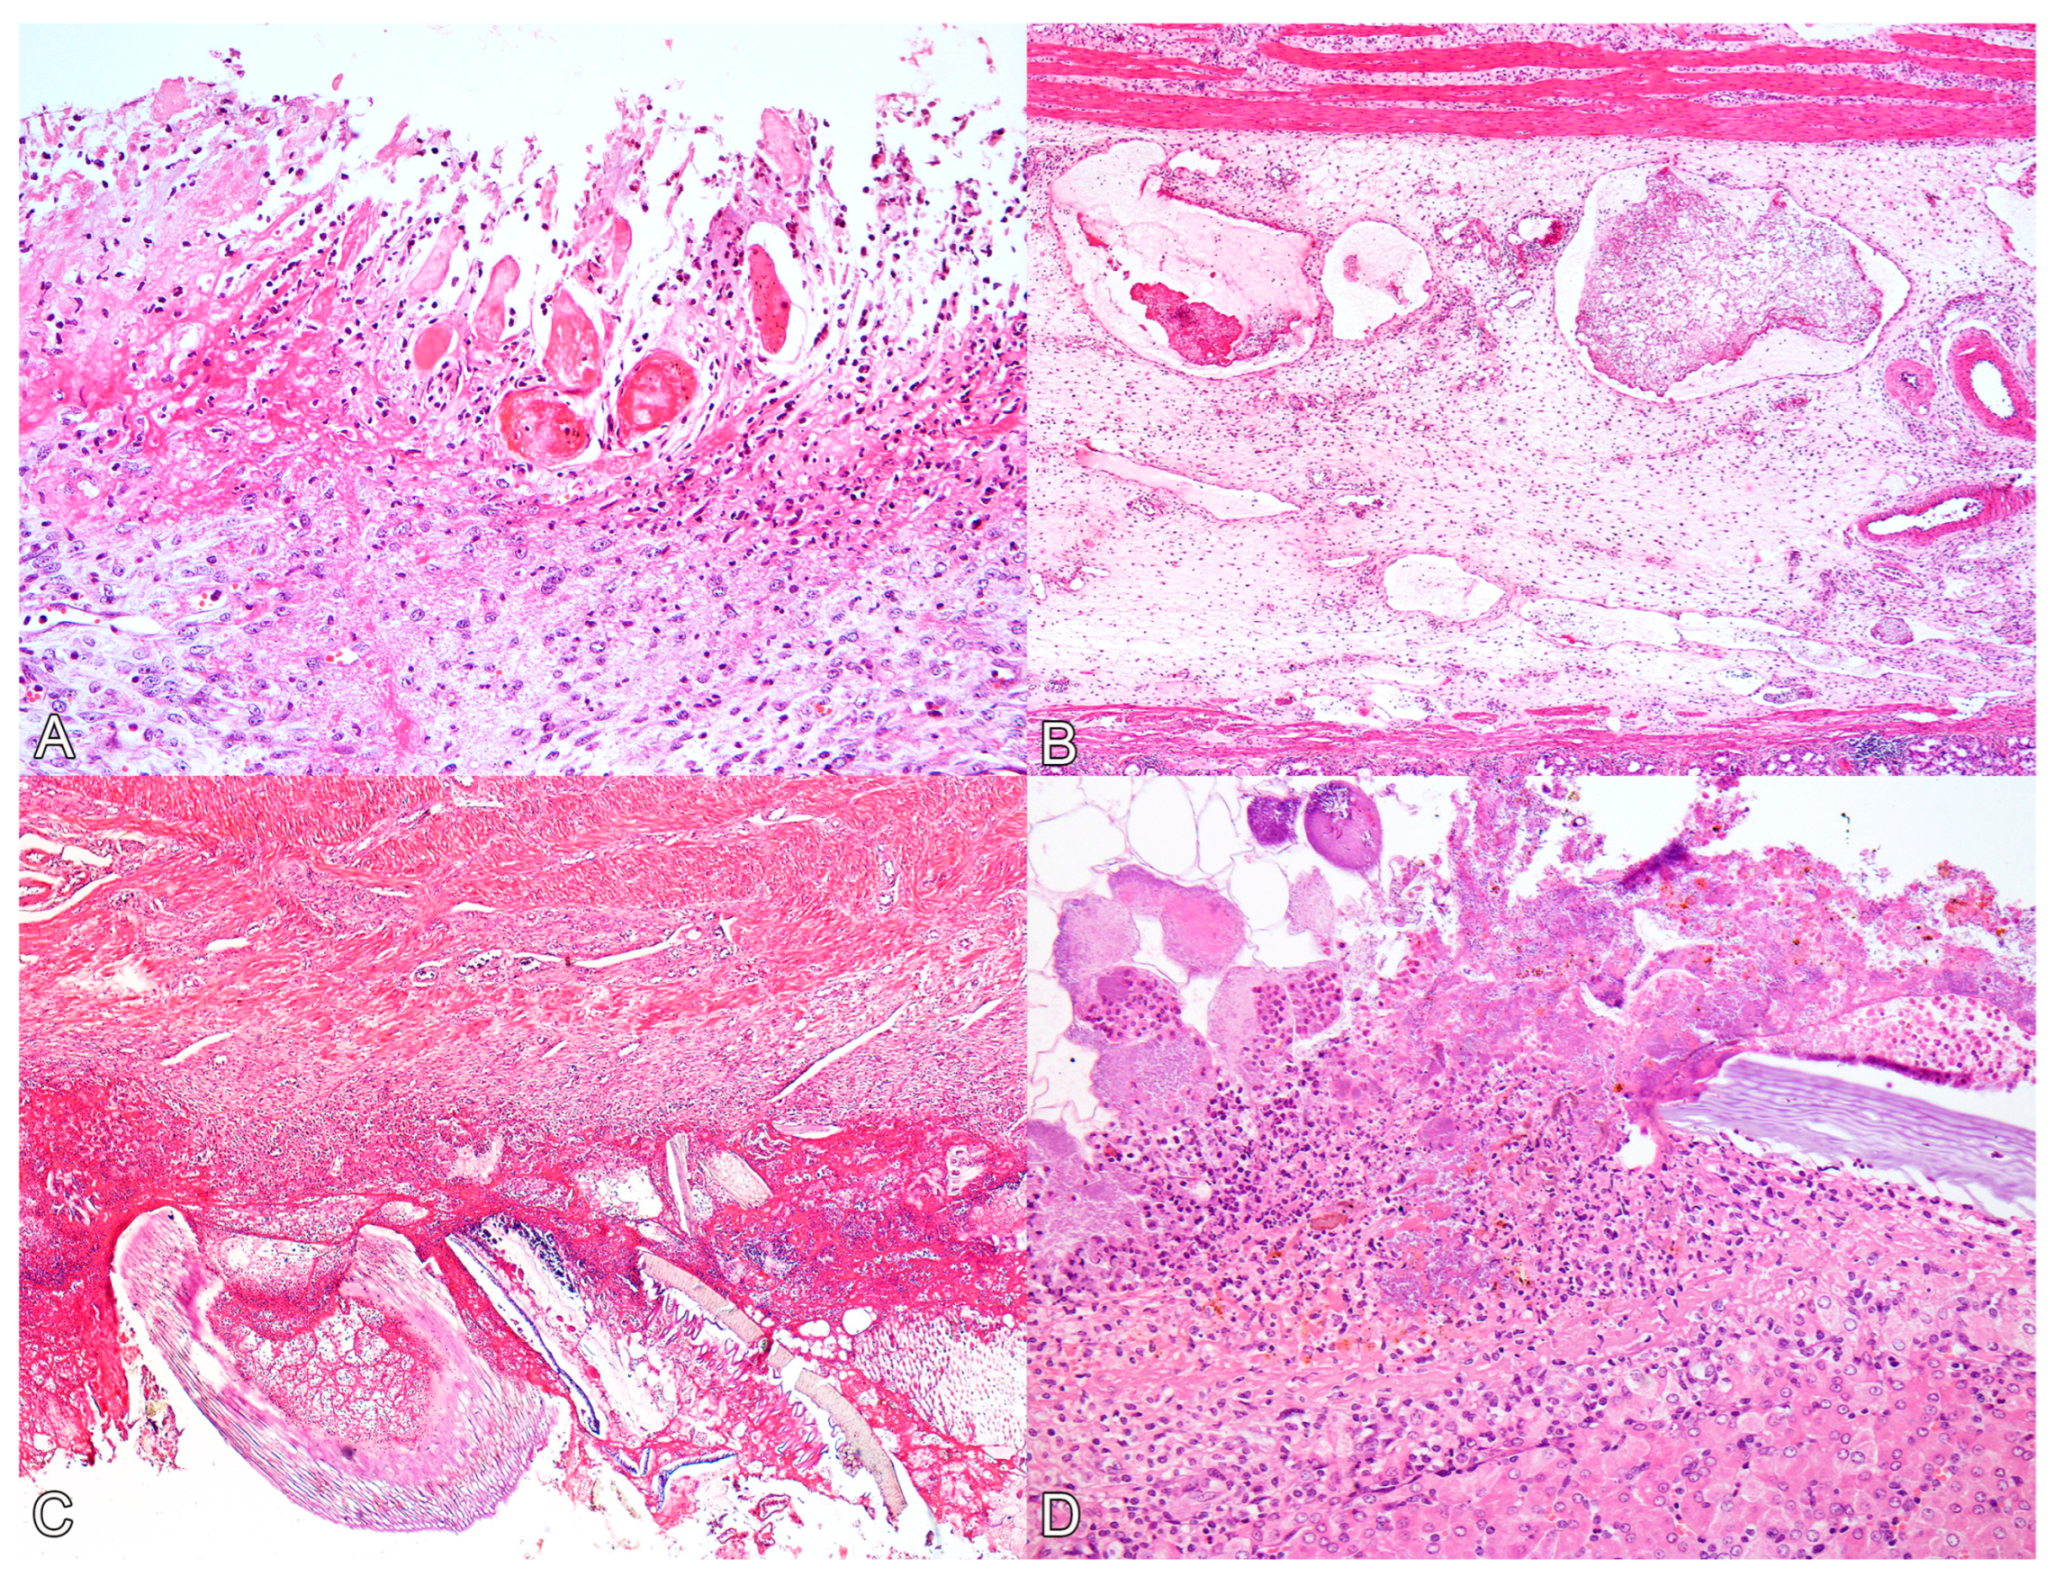

3.2. Postmortem Examination